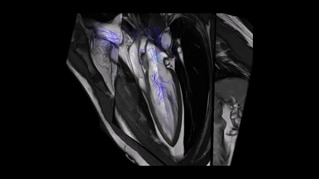

Within cardiovascular diseases, the functional assessment of the heart is an essential imaging application. SIGNA Sprint is powered by built-in AI technologies—Sonic DL™, AIR Recon DL and AIR x™—enabling high-quality imaging even in the most demanding anatomies.

The growing clinical need within oncology and cardiology requires an MRI scanner that can rise to the challenge. With a high gradient performance of 65/200, SIGNA Sprint helps deliver crystal-clear imaging for ultimate diagnostic confidence. Improved signal-to-noise ratio (SNR) and diffusion, with deep-learning solutions that could enhance diagnostics and treatment response monitoring in your oncology patients.¹ Additionally, the shift from qualitative to quantitative cardiac MRI reduces the time and expertise needed to interpret scans and offers greater consistency and reliability. Helping you to unlock the power to explore further - even in your most challenging cases.

Image generated from Circle CVi.